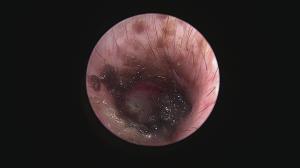

今回アップした動画は慢性外耳炎の中でも管理が困難な「耳垢腺過形成」による症例への治療動画になります

このような症例は管理が困難なため「全耳道切除」が一般的ですが、耳を摘出する手術は侵襲性が高いためなるべく避けたいところです。顔面神経麻痺などの副作用が懸念されます。

当院では内視鏡レーザー治療による緩和処置をすることで点耳薬による症状の改善を期待することができます

このような症例は案外多いため、一度精査を行い適切なケアをしてあげることがおすすめされます